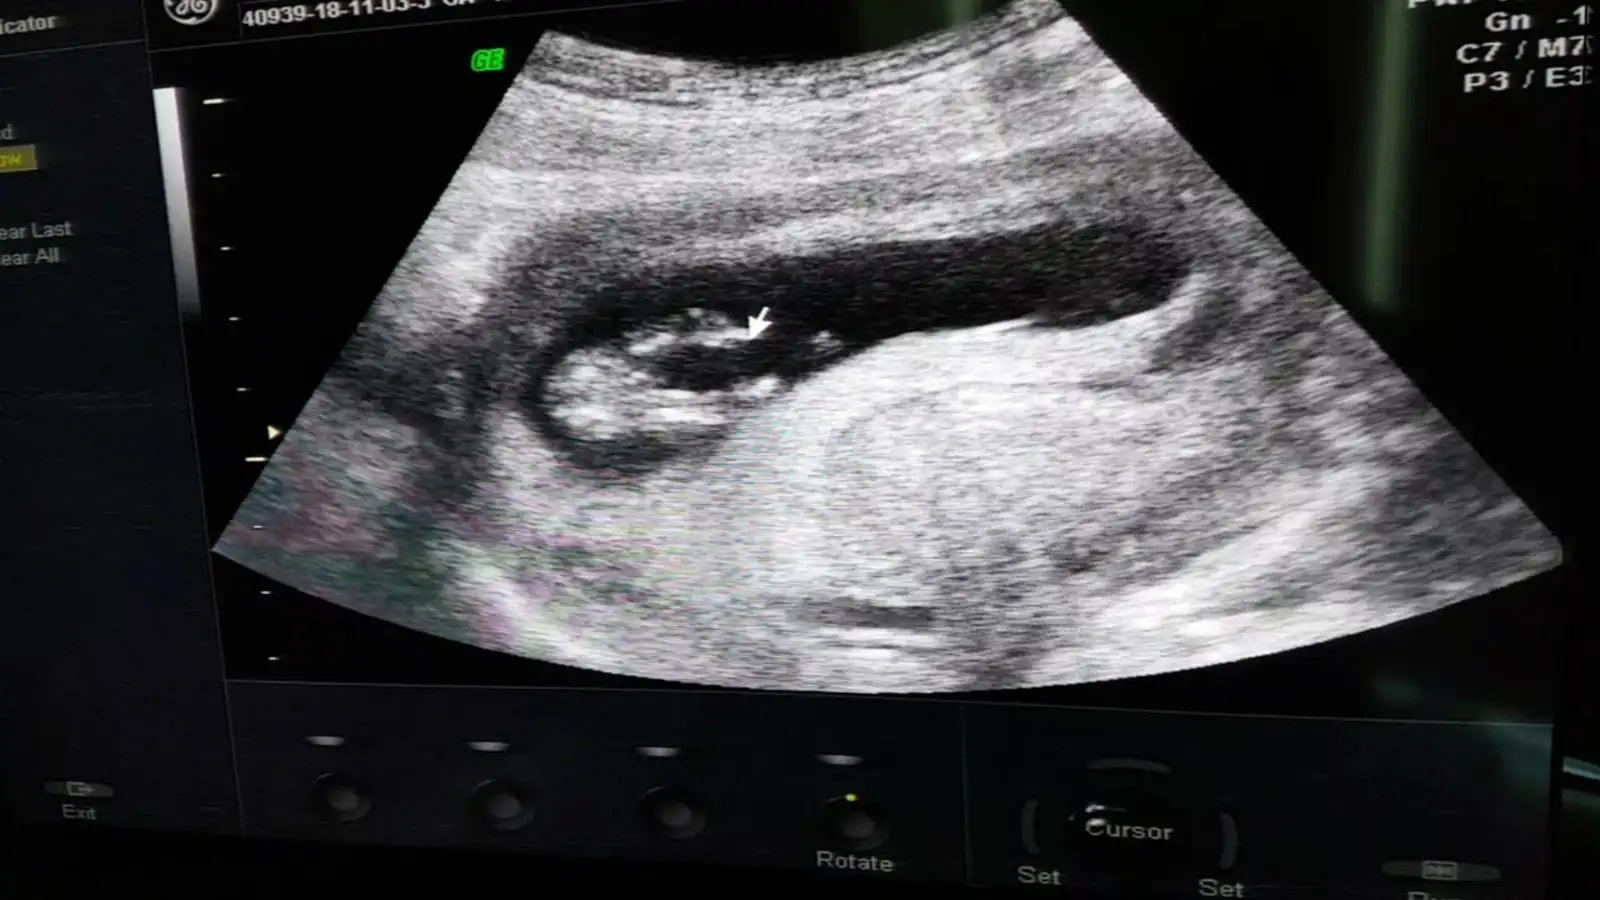

pipi gibi bişey nasıl acaba buna benziyor muydu

Allah bağışlasın. ultrason görüntüsü koyabilir misiniz karşılaştırsak. ben de erkek hissediyordum ama kız dedi %70 ihtimal. karşılaştırma yapalım

:mad:Kızlar ekleyebildim mi bilmiyorum. Benim yavruma da bakar mısınız? Kız mııı erkek miii?

Burda 12+6 doktor göremedi ve konrtole daha 3 hafta var. Ben de merak edip duruyorum. Yavrum secdeye kapanmış gibi poz verdi :nazar::KK200::nazar::KK200: